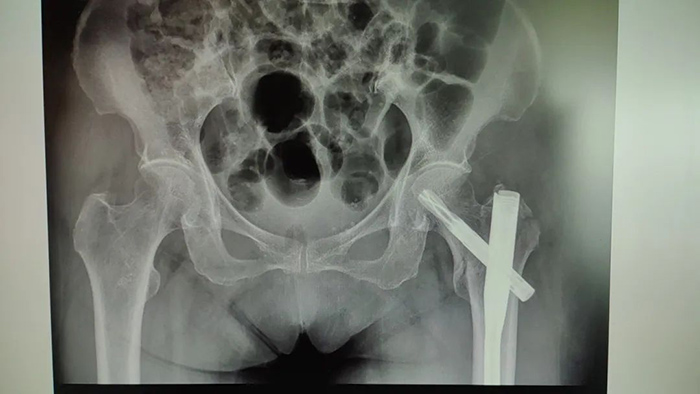

虽说做手术是最有效的方式 但叶老太的手术风险很大 ◆患者血红蛋白水平较低,一旦出现手术创伤**,有可能引起消化道大出血,危及生命。 ◆患者年事已高,有高血压、冠心病、糖尿病等病史,对手术的耐受能力较差,手术并发症及手术切口不愈合、感染的风险大。 ◆患者重度骨质疏松,腰椎T值仅为-4.2,手术中轻轻一敲就有可能导致骨折劈裂。 面对复杂病情,医务科组织消化内科、血液科、手术麻醉科、心血管内科、内分泌科、中医骨伤科联合会诊,制定严谨的手术预案。 经过充分的术前准备,叶老太血红蛋白浓度补充到94g/L,陈瑞松副主任医师、冯安平主治医师为其进行左股骨粗隆间粉碎性骨折闭合复位内固定术。手术顺利完成,患者生命体征平稳。 患者术后影像 术后 中医骨伤科医护团队精心护理 叶老太恢复良好 目前已出院回家休养 ▲出院时,患者及家属向中医骨伤科医护团队送来锦旗表达感谢。 如果老人有髋部骨折方面的困扰 可至我院中医骨伤科进一步咨询 中医骨伤科出诊专家一览表